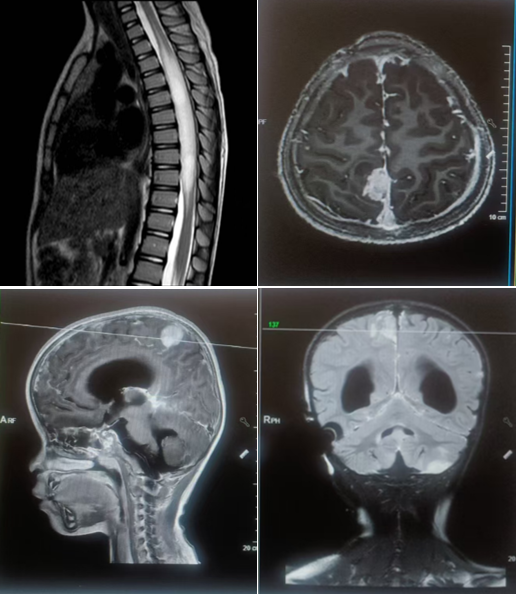

此次远程会诊特邀北京丰台右安门医院肿瘤科主任申戈教授、昆明市儿童医院小儿神经外科赵迁浩教授、昆明三博脑科医院名誉院长张永力教授、放疗中心郑虹教授、神经外科王浩然教授等多位专家共同参与。 通过远程会诊平台实现了病历资料、影像数据、病理报告的实时共享,让远隔千里的专家们能够同步掌握患儿的完整病情。会诊中,昆明三博脑科医院放疗中心团队首先详细汇报了三名患儿的病情特点、既往检查结果及前期治疗情况。随后,京滇两地专家围绕每个病例展开深度研讨,从肿瘤分型鉴别、放疗方案优化,到并发症预防、儿童生长发育保护等多个维度各抒己见、充分论证。